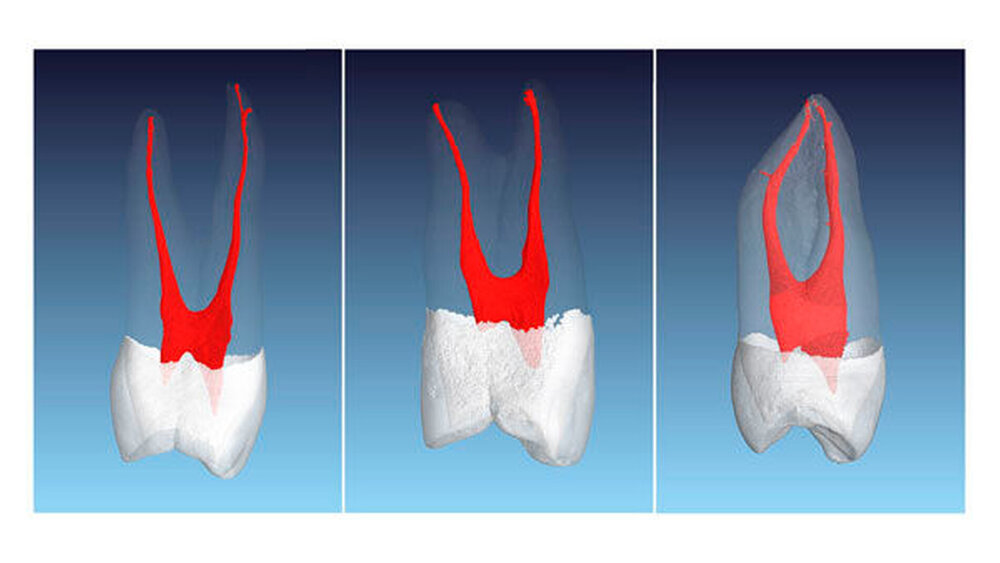

Beim ersten Prämolaren sind fast immer zwei vollständig getrennte Kanalsysteme aufzufinden. Von koronal nach apikal sind die Kanäle meist rund im Querschnitt – nach eigenen Beobachtungen bei hunderten von eingescannten Zähnen sind die Kanalquerschnitte des ersten oberen Prämolaren mit zwei Kanälen im Vergleich zu allen anderen Kanälen im menschlichen Gebiss am ehesten als rund zu bezeichnen – und werden sehr schmal im apikalen Bereich mit zum Teil erheblichen Krümmungen (Abbildung 2).